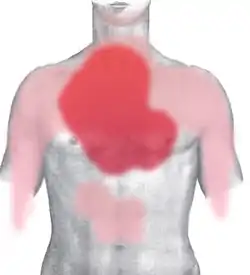

Chest pain that may or may not radiate to other parts of the body is the most typical and significant symptom of myocardial infarction. It might be accompanied by other symptoms such as sweating.[28]

Chest pain is the most common symptom of acute myocardial infarction and is often described as a sensation of tightness, pressure, or squeezing. Pain radiates most often to the left arm, but may also radiate to the lower jaw, neck, right arm, back, and upper abdomen.[29][30] The pain most suggestive of an acute MI, with the highest likelihood ratio, is pain radiating to the right arm and shoulder.[31][30] Similarly, chest pain similar to a previous heart attack is also suggestive.[32] The pain associated with MI is usually diffuse, does not change with position, and lasts for more than 20 minutes.[25] It might be described as pressure, tightness, knifelike, tearing, burning sensation (all these are also manifested during other diseases). It could be felt as an unexplained anxiety, or even pain might be absent at all.[30] Levine's sign, in which a person localizes the chest pain by clenching one or both fists over their sternum, has classically been thought to be predictive of cardiac chest pain, although a prospective observational study showed it had a poor positive predictive value.[33]

Chest pain may be accompanied by sweating, nausea or vomiting, and fainting,[25][31] and these symptoms may also occur without any pain at all.[29] In women, the most common symptoms of myocardial infarction include shortness of breath, weakness, and fatigue.[35] Shortness of breath is a common, and sometimes the only symptom, occurring when damage to the heart limits the output of the left ventricle, with breathlessness arising either from low oxygen in the blood, or pulmonary edema.[29][36] Other less common symptoms include weakness, light-headedness, palpitations, and abnormalities in heart rate or blood pressure.[17] These symptoms are likely induced by a massive surge of catecholamines from the sympathetic nervous system, which occurs in response to pain and, where present, low blood pressure.[37] Loss of consciousness due to inadequate blood flow to the brain and cardiogenic shock, and sudden death, frequently due to the development of ventricular fibrillation, can occur in myocardial infarctions.[38] Cardiac arrest, and atypical symptoms such as palpitations, occur more frequently in women, the elderly, those with diabetes, in people who have just had surgery, and in critically ill patients.[25]